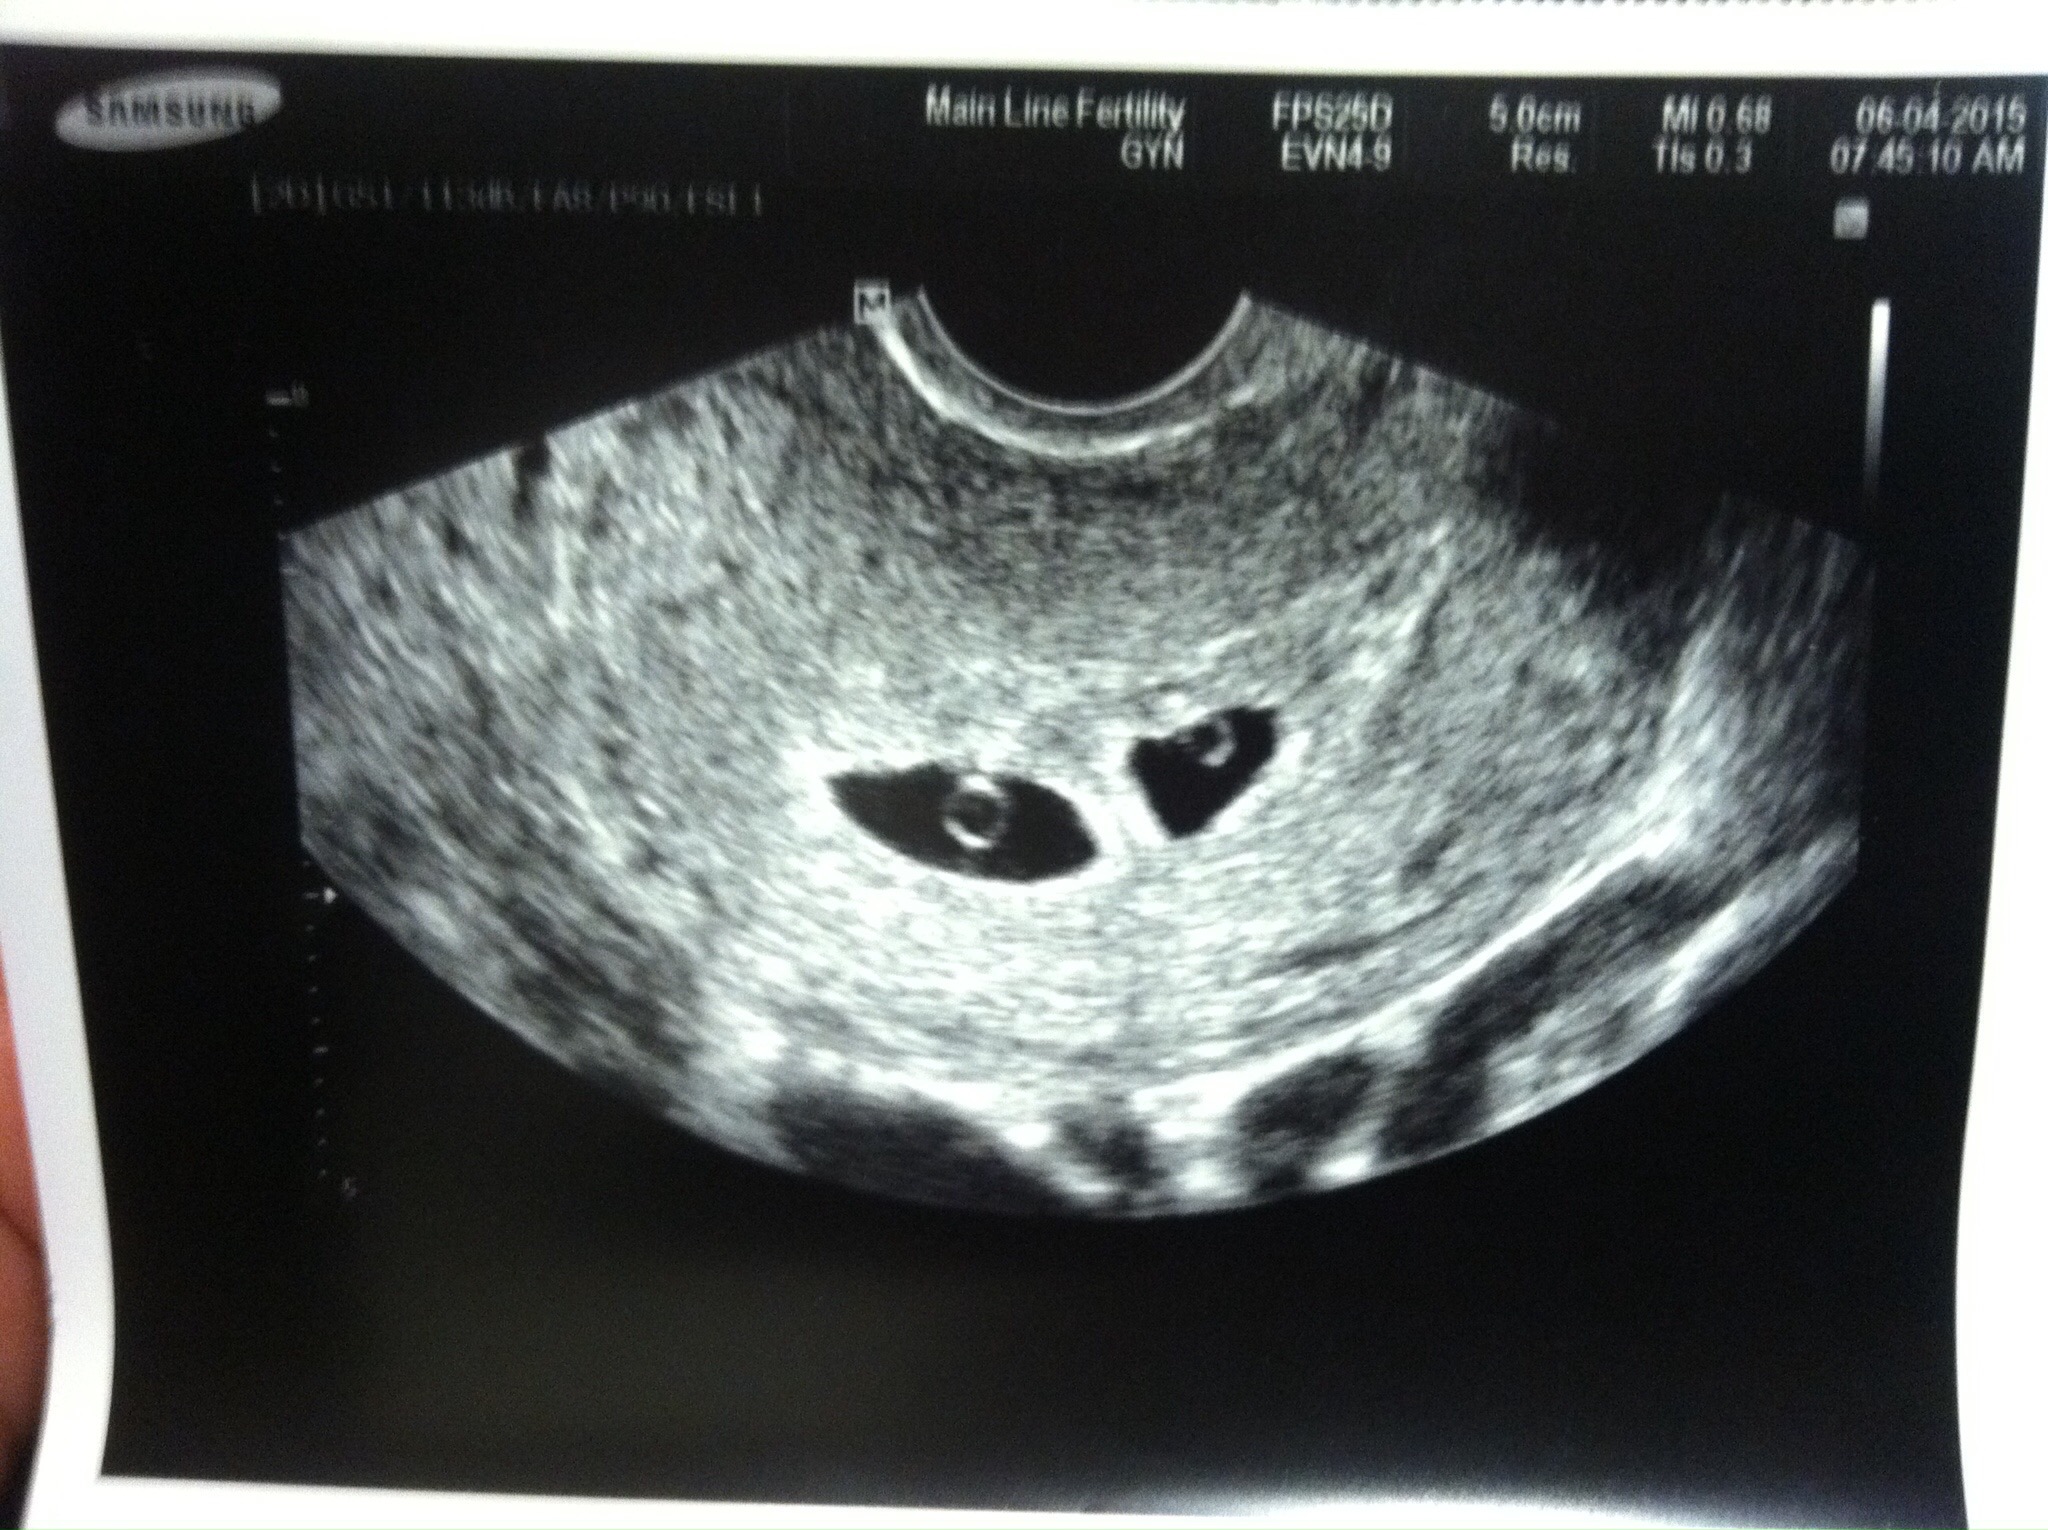

I'm thinking 2 girls but who knows. I find the Ramzi theory very interesting n I finally figured out how to post pictures. These are TV at 7 weeks 2 days.

@happyandhopeful3 I can't tell on the left and boy on the right in the first image, can't tell in second image @MamaZen I'm thinking girly based on placenta @KateBee do you have any clearer images?

So cool! My doctor zoomed in on the baby-I can't quite tell which side it's on! I'm attaching the 2 pictures I have from our 9.5 week ultrasound. Any guesses?

@happyandhopeful3 No worries it's fun for me too Ramzi method was 100% accurate for me it's a girl!!! I think you have two girls wait are these transnational ultrasounds?